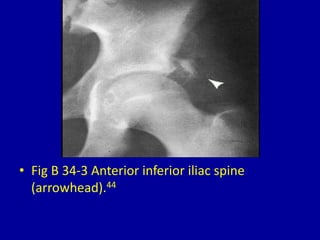

This document provides descriptions and images of avulsion injuries at various anatomical locations in the body. Avulsion injuries refer to the tearing away of a tendon, ligament, or muscle from the bone. The document lists 17 figures showing examples of avulsion injuries at locations such as the ischial tuberosity, anterior superior iliac spine, anterior inferior iliac spine, symphysis pubis, lesser trochanter, greater trochanter, fibular head, tibial eminence, posterior cruciate ligament, tibial tuberosity, inferior pole of the patella, calcaneal tuberosity, anterior and posterior capsule of the ankle joint, greater and lesser tuberosity of the